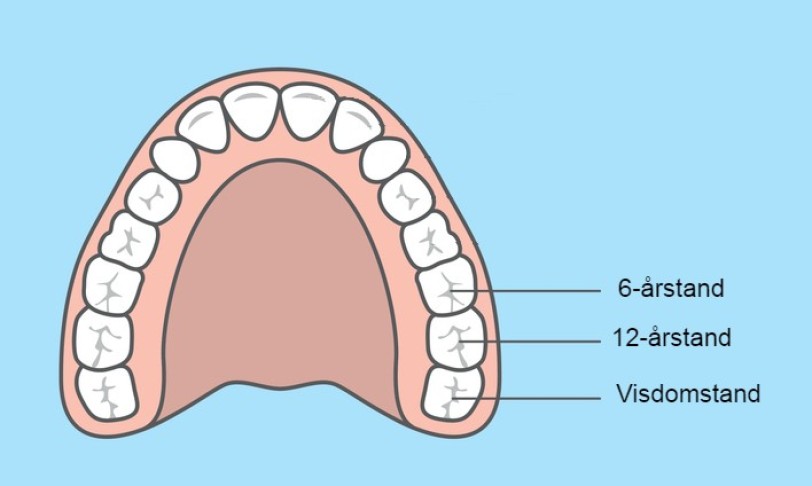

Nuno Vibe Hermann forklarer, at en tand nogle gange er så svært påvirket af MIH, at det bedste er at trække den ud. Her vil der altid være tale om kindtænder, da det er dem, der bliver ramt af den svære form for MIH. Og selvom det lyder dramatisk, kan det faktisk være en rigtig god løsning. Det efterlader nemlig plads til de raske 12-årstænder og visdomstænder, der senere bryder frem:

- Hvis vi trækker tanden ud på det rigtige tidspunkt, kan vi få 12-årstanden til at bryde frem og ‘stille sig’ på 6-årstandens plads, og så kan visdomstanden stille sig på 12-årstandens plads. På den måde kan den unge person ende med at få et helt normalt tandsæt, der fungerer godt. Det er jo også en fordel i patientens fremtidige liv, for hvis man har nogle meget behandlede tænder, så vil det være noget, som man skal have lavet om flere gange i sit voksne liv, og det koster mange penge, siger Nuno Vibe Hermann.

Hvis 6-årstanden er meget påvirket af MIH, er det i nogle tilfælde bedst at trække den ud. Når 12-årstanden bryder frem, kan den tage den tomme plads fra 6-årstanden. Senere tager visdomstanden 12-årstandens plads, og tandrækken “lukkes”.